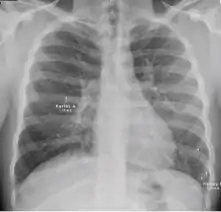

Chest x-ray of pleural thickening post-primary tuberculosis

1. Pleural thickening - Irregularity or abnormal prominence of the pleural margin, including apical capping (thickening of the pleura in the apical region). Pleural thickening can be calcified.

2. Diaphragmatic tenting - A localized accentuation of the normal convexity of the hemidiaphragm as if "pulled upwards by a string."

3. Blunting of costophrenic angle (in adults)—Loss of sharpness of one or both costophrenic angles. Blunting can be related to a small amount of fluid in the pleural space or to pleural thickening and, by itself, is a non-specific finding (except in children, when even minor blunting may suggest active TB). In contrast a large pleural effusion, or the presence of a significant amount of fluid in the pleural space, may be a sign of active TB at any age.

4. Solitary calcified nodules or granuloma - Discrete calcified nodule or granuloma, or calcified lymph node. The calcified nodule can be within the lung, hila, or mediastinum. The borders must be sharp, distinct, and well defined. This was considered a Class B3 TB in the past; however, Class B3 has been omitted from the classification scheme because it has not been found to be associated with active TB.